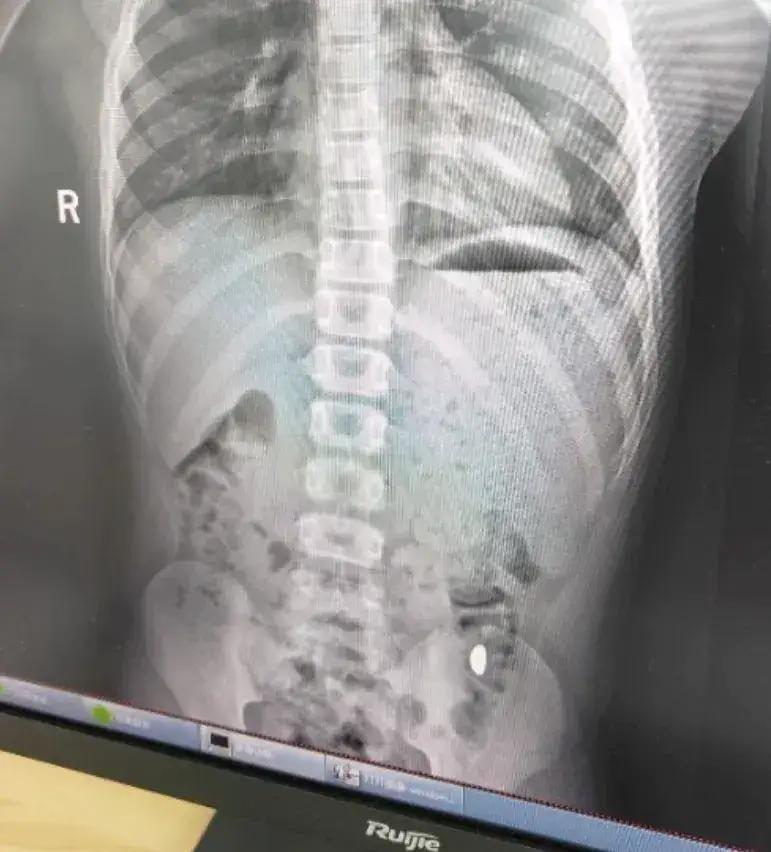

江苏昆山一位11岁男孩为了"锻炼舌头力量",竟然把妈妈刚买的10克金豆吞了下去,妈妈纪女士发现后真是又气又笑,天天叮嘱儿子"这个屎有点贵,千万别在外面上厕所"。这事在网上火了,吸引50多万人围观。 纪女士一开始还以为儿子开玩笑,确认后倒也不慌。因为她侄女以前吞过硬币,医生说能自然排出。上网一查,发现金子也能拉出来。于是她耐心等了5天,亲自检查了两次"黄金便便",可惜没找到那颗金豆。 第6天纪女士带孩子去了昆山市第五人民医院。检查显示金豆还在胃里,但孩子没啥不适。 神奇的是,当天下午金豆就"顺利出厂"了。 网友们都被这事逗乐了:"这娃拉的是真·黄金""妈妈这是守着金矿啊"。不过笑归笑,安全最重要。家里有熊孩子的,赶紧检查下有没有小物件乱放吧!